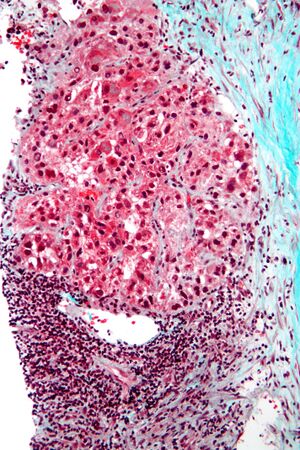

Pathology

Macroscopically, liver cancer appears as a nodular or infiltrative tumor. The nodular type may be solitary (large mass) or multiple (when developed as a complication of cirrhosis). Tumor nodules are round to oval, gray or green (if the tumor produces bile), well circumscribed but not encapsulated. The diffuse type is poorly circumscribed and infiltrates the portal veins, or the hepatic veins (rarely).[16]

Microscopically, the four architectural and cytological types (patterns) of hepatocellular carcinoma are: fibrolamellar, pseudoglandular (adenoid), pleomorphic (giant cell), and clear cell. In well-differentiated forms, tumor cells resemble hepatocytes, form trabeculae, cords, and nests, and may contain bile pigment in the cytoplasm. In poorly differentiated forms, malignant epithelial cells are discohesive, pleomorphic, anaplastic, and giant. The tumor has a scant stroma and central necrosis because of the poor vascularization.[39] A fifth form – lymphoepithelioma like hepatocellular carcinoma – has also been described.[40][41]